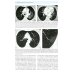

Книга составлена из двух разделов. В первом (глава 1) описаны основные симптомы патологии легких, выявляемые при КТ. Каждый из них представлен с позиции отображающих его морфологических изменений. В краткой форме описаны заболевания, проявляющиеся конкретным симптомом. Второй раздел книги состоит из трех глав, в которых отражены современные взгляды на наиболее часто встречающуюся патологию легких (пневмония, туберкулез, рак) и показаны возможности КТ в выявлении этих заболеваний. Издание предназначено для врачей лучевой диагностики, терапевтов, интернов и студентов старших курсов, интересующихся проблемами рентгенологии.| Издательство | МЕДпресс-информ |